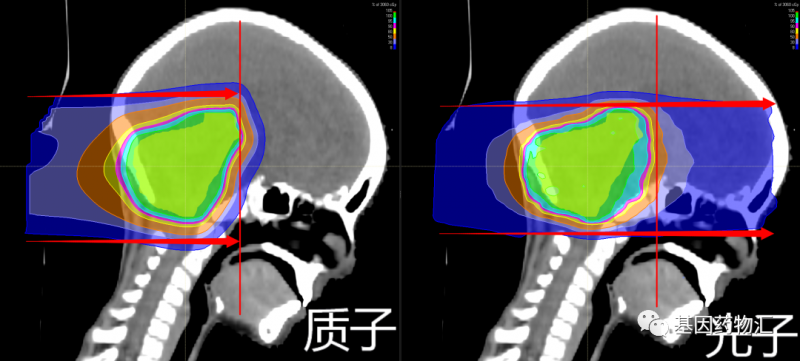

质子疗法属于放疗,是一种采用质子束取代目前临床上最常用的光子束(X射线)进行放射治疗的疗法。

除能量强度外,由于粒子的重量不同,两种射线束还具有不同的特性。质子是相对较重的带正电的粒子,它们会在击中目标时停止。而X射线由光子组成,光子是几乎没有质量的粒子,因此它们会一直穿过身体,包括健康的组织。

1、放射剂量更集中于病灶部位

采用光子疗法时,接近50%的放射剂量会在抵达病灶部位前或经过病灶部位后才释放;而采用质子疗法治疗,质子束能够携带的能量更高,同时在抵达病灶部位时才会释放最大的剂量。

换句话说,采用光子疗法,大量的放射剂量照射在了并不需要承受放射的健康组织上。人体正常组织能够承受的放射剂量有限,将更多的放射剂量集中于病灶部位可以获得更好的疗效与预后。

2、安全性更好

击中病灶部位时释放最大剂量并停止——这样“点到即止”的特点,使质子疗法获得了比传统光子放疗更好的安全性

采用质子疗法,能够更好地将放射剂量集中于病灶部位,而非“穿过”患者的身体,因此对于正常组织造成的放射更少,导致的急性毒性反应及远期毒性反应更少。